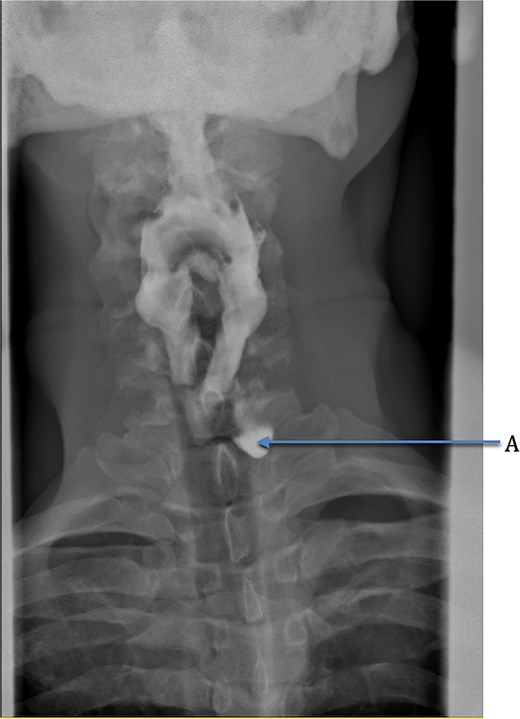

We present the case of a 57-year-old male patient who presented with dysphagia, regurgitation of undigested food, alongside a globus sensation. He had no significant medical history. He underwent a fluoroscopic swallow study, which revealed an anterolateral pharyngeal diverticulum consistent with a KJD with a neck of 5 mm and a length of 25 mm (Fig. 1). Given his symptoms, operative management was undertaken in which an incision was made along the medial border of the sternocleidomastoid. The platysma was divided, and dissection performed down to the level of the thyroid membrane with preservation of strap muscles. The left recurrent laryngeal nerve (RLN) was identified and preserved (Fig. 2). The esophageal diverticulum and sac were isolated from surrounding structures, and the neck was ligated using a 2/0 Vicryl prior to being excised. The ligation site was oversewn with 3/0 Vicryl. A drain was left, and the incision was closed in layers. Post-operatively, the patient underwent fluoroscopic swallow study, which did not show a leak or residual diverticulum, and after removal of the drain, the patient was discharged home day 1 postoperatively (Fig. 3).

Coronal view of fluoroscopic swallow showing Killian-Jamieson esophageal diverticulum labeled A.